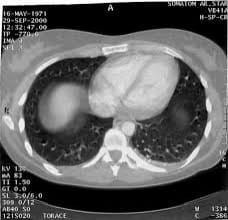

TAC TORACE E ADDOME

Tecnologia che consente di acquisire immagini estremamente dettagliate di organi interni, vasi sanguigni e tessuti molli del corpo.

- TAC Torace (inclusa TC Torace a strato sottile per parenchima polmonare)

- TAC Addome Superiore

- TAC Addome Inferiore (Pelvi)

- TAC Addome Completo

- Uro-TAC (Tecnica lenta per lo studio dell'apparato urinario)

- TAC Total Body (Encefalo-Torace-Addome-Pelvi)